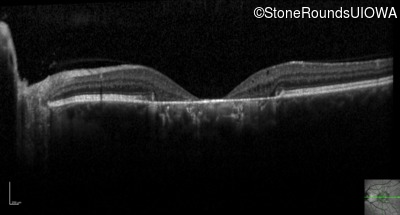

Optical Coherence Tomography - Right - 20/40 -1

Exemplar / OCT Stack